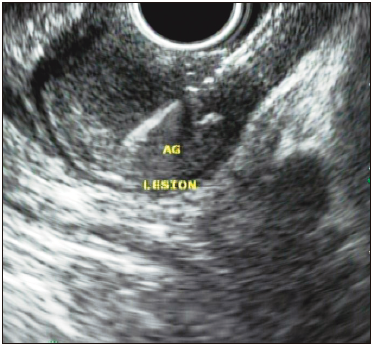

Posteriormente, el USE informó una lesión redondeada, hipoecoica, de 25 x 16 mm de diámetro, localizada en la capa muscularis mucosae, en íntimo contacto con la submucosa (Figura 3). Se realizó la punción con aguja de 19G, informándose tumor de células granulares, inmunohistoquímica (IHQ) con expresión de proteína S100 y marcador CD68 fuertemente positivos (Figuras 4, 5, 6 y 7).

Figura 3. Ecoendoscopia con punción